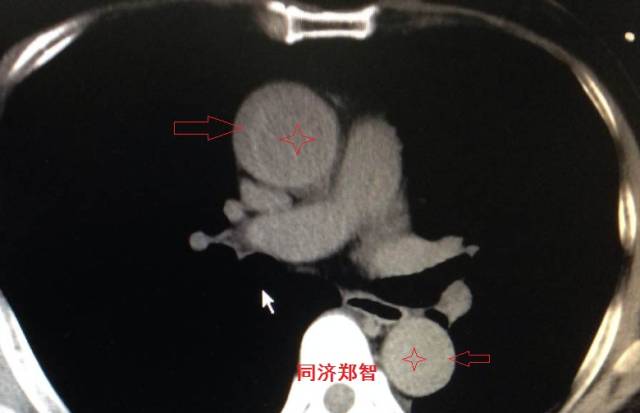

胸部平扫CT提示升主动脉增宽(红色星形标记),CTA证实A型主动脉夹层伴升主动脉夹层动脉瘤形成。

图3